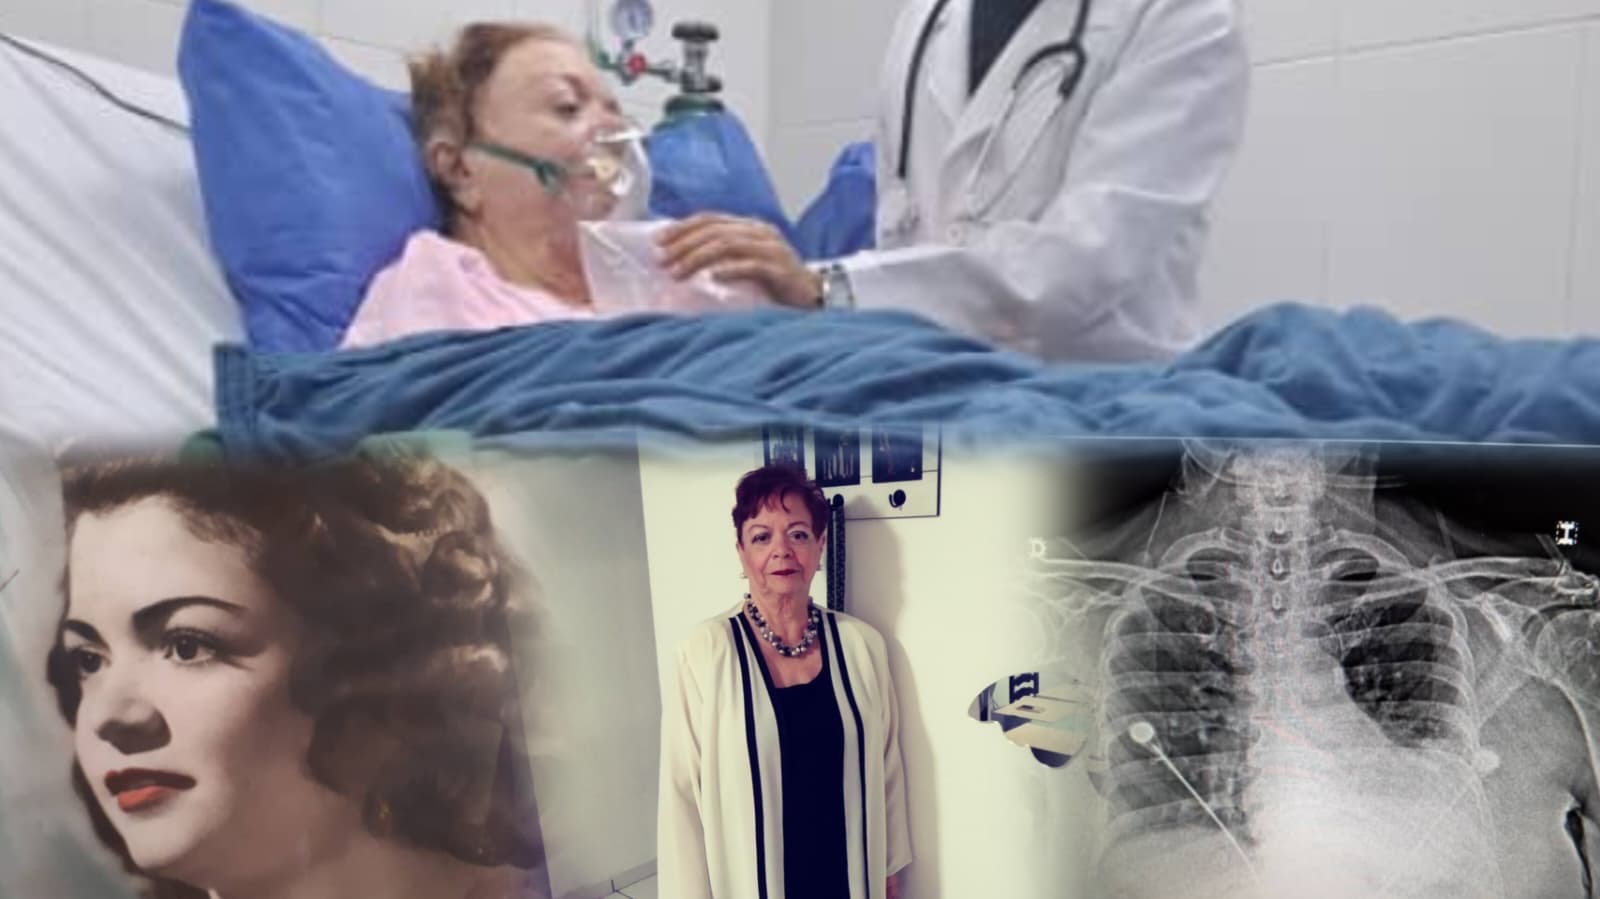

Hola, soy Ruben Romero mi mamasita siempre ha estado presente para mi en las buenas, en las malas y en las enfermedades. También es una buena católica de inmensa bondad, generosidad y amor por el prójimo. Siempre ella ha ayudado sin esperar nada a cambio, ha sido una amiga incondicional. En estos momento esta pasando por un cuadro medico muy complicado:

1.-Tromboembolismo Pulmonar de Rama Principal Derecha con Extensión hacia Ramas

Segmentarias

2.-Trombosis Venosa Profunda Femoro-Poplitea Pierna Izquierda en Fase de

Recanalización.

3.-Neumonia Basal Izquierda

4.-DMT2 en hiperglicemia.

5.-HTAE2 mal controlada.

6.-Enfermedad Intersticial Pulmonar Crónica

7.-Crisis Ansioso-Depresiva

Ahora se encuentra recluida en la Unidad de Terapia Intensiva. Se que Dios primeramente esta poniendo su santa bendición. Hermanos hoy recurro a sus inmensos corazones en cuanto ayuda economica puedan hacer esto para pagar los gastos medicos que yo no puedo afrontar en su totalidad. Se que muchos somos hijos de mujeres tan grandes como la mia por lo que saben por lo que estoy pasando hoy dia. De ante mano muchas gracias y que mi Dios les multiplique en salido y bendiciones.